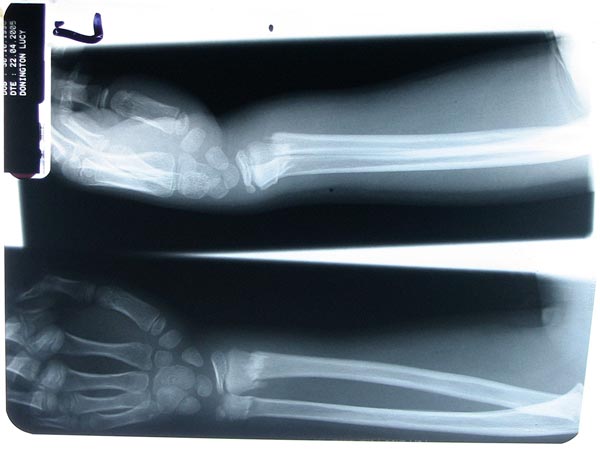

Lucy's Broken Arm...

... following a fall from the monkey bars in Oakwood Park.

22 April, 2005